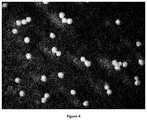

FIG. 4. A micrograph showing control units after admixture with tap water.

A composition according to certain embodiments of the disclosure was mixed with tap water and placed on a Petri dish. The same procedure was performed on a composition with no xanthan gum outer coating (control).FIGS. 1 and 2 show micrographs of the compositions according to certain embodiments of the disclosure as set forth in Tables 2 and 3, respectively, exemplifying the halo formed around each pellet. The halo is indicative of imbibition of water by the outer coating and its swelling.FIGS. 3A-3E show a sequence of micrographs of the composition according to certain embodiments of the disclosure as set forth in Table 7, the micrographs taken at time 0, 100, 200, 300 and 600 seconds after admixture with tap water, respectively. The micrographs exemplify the swelling of the outer coating due to imbibition of water.FIG. 4 shows the absence of halo in a control sample andFIGS. 5A and 5B show the absence of a halo in a control sample at time 0 and 600 seconds after admixture with tap water, respectively.